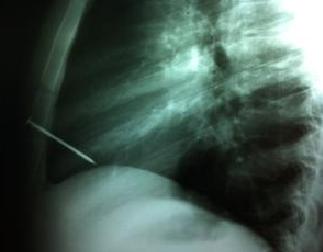

09-01-2013 | En el hospital El Cruce /Néstor Kirchner de Florencio Varela

Extraen con 茅xito un clavo del coraz贸n de un hombre

La cirug铆a se realiz贸 en el Hospital El Cruce / Nestor Kirchner de Florencio Varela; el joven, de 19 a帽os, hab铆a sufrido un accidente mientras trabajaba en una maderera. Solo tres personas han sobrevivido a lecciones como estas, en todo el mundo.